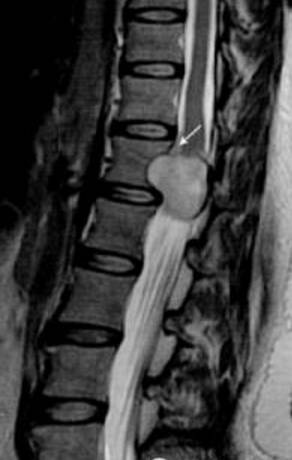

典型图

脊柱MRI提示椎管内占位及相应水平椎体后缘扇贝样压迹(白箭)